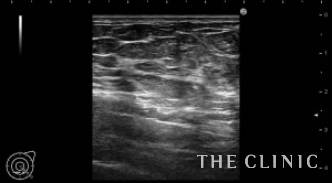

この方は、3年前に他院でバッグ除去と脂肪注入による豊胸を受けられた方です。半年程前からしこりに気付き、注射による治療をされていましたが現在痛みもあるため当院を受診されました。

エコーにて、右にオイルシスト、左にオイルシストと4㎝の混合性腫瘤を認めました。(オイルシストの症例はNo.32でご紹介します)